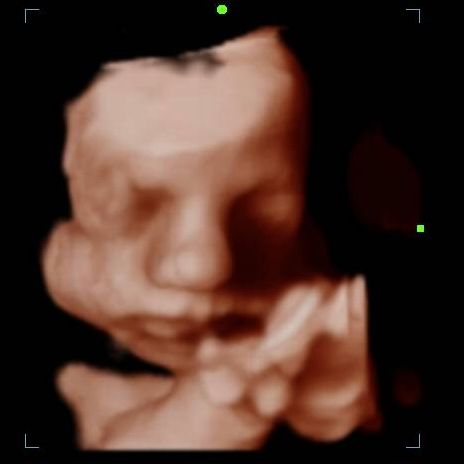

2d, 3d,4d & HD live

Enjoy a private, affordable ultrasound from the comfort of your home, perfect for moms between 7–41 weeks. Share the moment with loved ones by connecting directly to your TV for real-time viewing in 2D, 3D, or 4D. Ideal for baby showers or gender reveal parties!